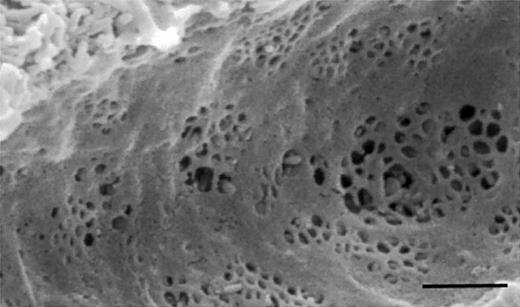

Scanning electron micrograph of the liver sieve, demonstrating fenestrations clustered into liver sieve plates. The scale bar indicates 1 μm.

Cirrhosis and old age both are associated with loss of the liver sieve.2,3 The “liver sieve” is a term used to describe the endothelial cells that line the hepatic sinusoids. These cells are perforated by multiple fenestrae of approximately 100-nm diameters, within very thin cytoplasmic extensions (Figure1). Lacking a basal lamina, sinusoidal fenestrae are truly discontinuous and thus allow unimpeded passage of macromolecules up to those with a diameter of about 100 nm including, potentially, viral vectors such as those involved in gene therapy. Indeed, we suggested 25 years ago that the normal liver sieve allows circulating viruses smaller than 100 nm to contact hepatocytes,4 and this has largely been substantiated since.5,6 The adeno-associated virus used by Mount et al has a diameter of about 20 nm.7